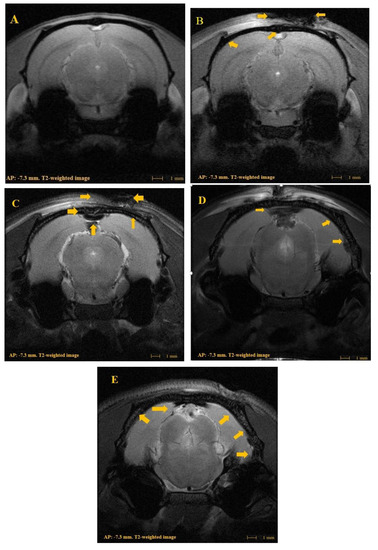

MRI observations clearly illustrated time-course morphological alterations, impacts of the TBI, and the progressive development of secondary injury in the brain. The time-course study of the brain and respective MRI images clearly revealed the prevalence of cerebral edema and intracranial hemorrhaging close to the cerebral cortex due to the weight drop inducing the TBI. The MRI image in Figure 2A demonstrates the normal condition of the rat brain, and in the corresponding MRI images of 2B (day1), 2C (week 1), 2D (week 2), and 2E (week 4), the arrow indicates cerebral edema and the progression of intracranial hemorrhaging of TBI rats in time-course intervals.

Last of all, the MRI results confirmed the presence of cerebral edema in the cortical region of experimental rats (Figure 2). Cerebral edema can be demarcated as an anomalous accumulation of water molecules within brain tissues and is a major reason for secondary neurological deterioration in subjects with brain injury [25]. It was evident that the TBI induced initial cytotoxic edema followed by ionic and ending with vasogenic edema. The development of cerebral edema is a complex process that includes different phases and may occur in parallel in variously injured brain areas [26]. Cerebral edema eventually leads to intracranial hypertension and is reported to also induce an over-reactive bladder condition [27]. The findings of Salk and Weinstein [28] confirmed that intracranial pressure can decrease the urinary flow rate on the basis of renal vasoconstriction causing a reduction in renal blood flow. Hence, there is a possibility for an over-reactive bladder condition as well as a decreased urinary flow state that can result from cerebral edema. In the current study, the development of cerebral edema was clearly denoted in MRI findings at different phases of the time course. The aforementioned discussion is closely associated with the current findings and also supports them.

Figure 2. (A) T2-weighted magnetic resonance imaging (MRI) of normal control (NC); (B) T2-weighted MRI of a rat with an experimentally induced traumatic brain injury (TBI) on day 1; (C) T2-weighted MRI of a rat with a TBI at week 1; (D) T2-weighted MRI of a rat with a TBI at week 2; (E) T2-weighted MRI of a rat with a TBI at week 4. Arrows indicate the severity of the TBI and cerebral edema; all TBIs shown here were induced by a weight-drop model at a 2 m height.